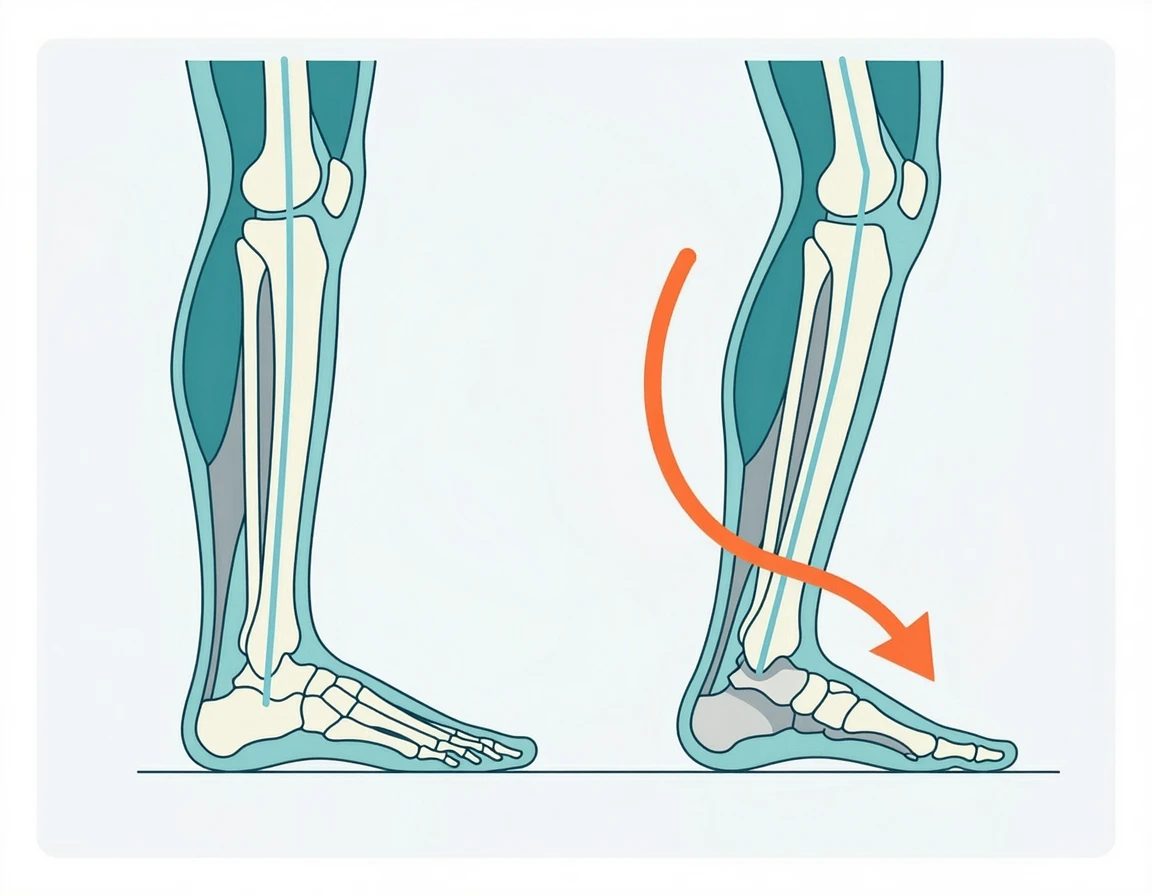

본격적인 비교에 앞서, 왜 평발은 전용 신발을 신어야 하는지 짚고 넘어갈게. 해부학적으로 평발(Pes Planus)은 발의 내측 종아치(Medial Longitudinal Arch)가 주저앉아 있는 상태를 말해요. 우리가 달릴 때 발이 지면에 닿는 순간, 체중의 2~3배에 달하는 충격을 흡수하기 위해 발목이 안쪽으로 살짝 꺾이게 되는데, 평발은 아치가 없어서 이 꺾임이 과도하게 발생하는 과회내(Overpronation) 현상이 나타나게 되죠. 이게 왜 치명적이냐면, 발목이 안으로 과하게 무너지면 연결된 경골(정강이뼈)이 안쪽으로 강제 회전하고, 결국 무릎 관절과 골반의 정렬까지 틀어지게 만들거든요. 흔히 겪는 신스플린트(정강이 통증)나 장경인대 증후군이 여기서 시작되는 거야. 따라서 평발 러너는 푹신하기만 한 신발보다는 발목이 안쪽으로 무너지는 것을 물리적으로 막아주는 단단한 지지대, 즉 '안정화(Stability Shoes)'를 선택하는 것이 선택이 아닌 필수랍니다.